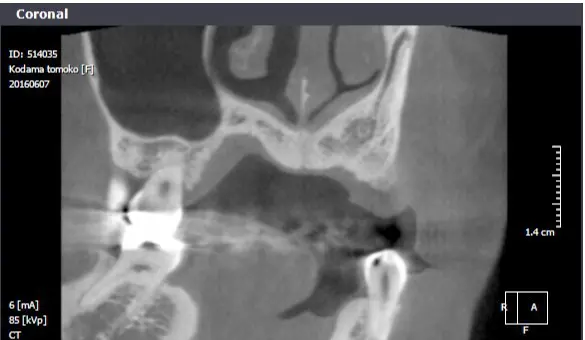

レントゲン写真

| 治療名称 | 右上中切歯が外傷による歯根破折。同部インプラント治療 |

| 患者の症状 | 歯が動いて痛む。 |

| 治療方法 | レントゲンで精査すると歯根が破折しており保存不可能なので抜歯。 もともと正中離開し審美的にも不良であった。正中離開した状態でそのまま治すのかこの際、審美的にも改善したいのか2つのオプションを提示すると矯正治療をした上で完璧に治したいとの要望があったので矯正治療を行いインプラント治療する計画を立てた。両隣在歯3本はジルコニアセラミック審美治療を行った。 |

| 治療結果 | 術後10年経過しているが患者様は非常に満足されている。 |

| リスク副作用 | 出血、腫脹、疼痛 |